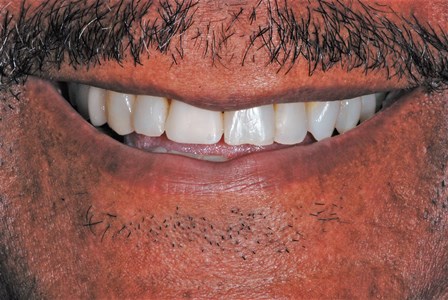

Before

After